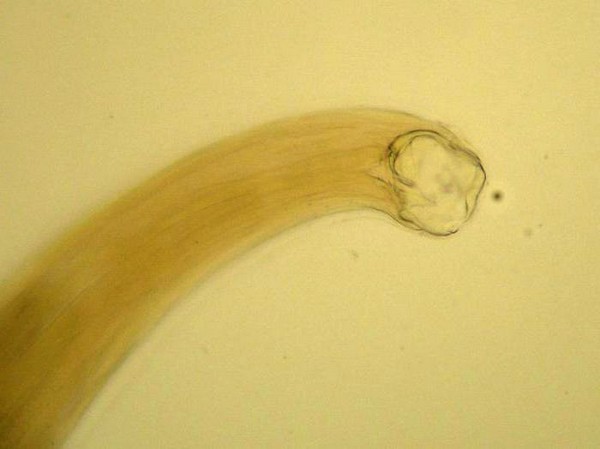

- с головной части тела идёт равномерное коническое сужение к хвостовой части;

- ротовая капсула гельминта состоит из двух пар присосочных дисков, с помощью которых паразит удерживается на стенках двенадцатиперстной или тонкой кишки.